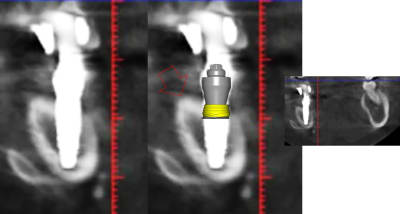

1 se baser sur la pano pour en tirer des conclusions est une erreur de débutant

2 sur les coupes scanner une partie du col est infra osseuse et l'autre non

3 lorsque tu te permets le genre de commentaire que tu fais il faut être en mesure d'étayer un argumentaire

> 1 se baser sur la pano pour en tirer des conclusions est une erreur de débutant

>

> 2 sur les coupes scanner une partie du col est infra osseuse et l'autre non

mais posit... y'a que toi qui pense que l'implant est aussi enfoui... ca saute aux yeux que tu fais tout pour grater 1mm d'enfouissement... pour qu'ils paraissent pas si mal posé que ca...

avec, par exemple, ton implant de 10mm qui est contenu dans 9mm... t'es le Gérard Majax des guides chir.

comme ici... si e carré fait 4,5 alors l’implant ne fait pas 10 mais moins de 9...

Tout comme l’autre implant pas 11,5 mais 10,3

heureusement que ta méthode est "précise" ;)

mais si tu t'intéressais un peu à la littérature tu saurais que ce n'est pas un problème dans ce cas clinique et tu ne serais pas obligé de mentir en dessinant n'importe quoi

En traçant le col de l'implant comme tu le fais tu ne tiens pas compte que le pilier fait 4,5 mm de hauteur, normalement tu devrais arriver à le comprendre tout seul !

Pour le reste de la discussion que le col ne soit tout infra osseux oui mais pas "5 spires" et tout les implants sont en bi corticale. Lorsque tu dis à quelqu'un qu'il est de mauvaise foi vérifie en premier tes arguments. Pour le col dans un cas comme celui là ce n'est pas un problème.

Dans ce cas l'épaisseur du sulcus est de 8 à 12 mm

L'enfouissement des implants était programmé pour stopper à 50 Ncm